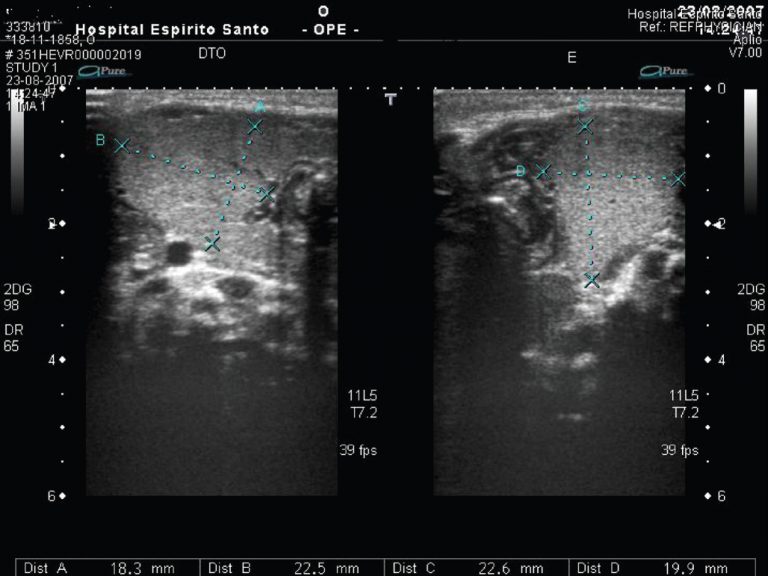

Congenital goiter is a rare cause of neonatal neck mass and may result from a fetal defectin synthesis of thyroxine, or administration of antithyroid drugs or iodides during pregnancy. The thyroid dysfunction often accompanies it. This report describes a case of a male term newborn with congenital goiter and primary hypothyroidism. Hormonal replacement treatment was started leading to normal levels of free thyroxine and triiodothyronine. In face of a maternal negative investigation, dyshormonogenesis was considered to be the most probable cause of hypothyroidism.